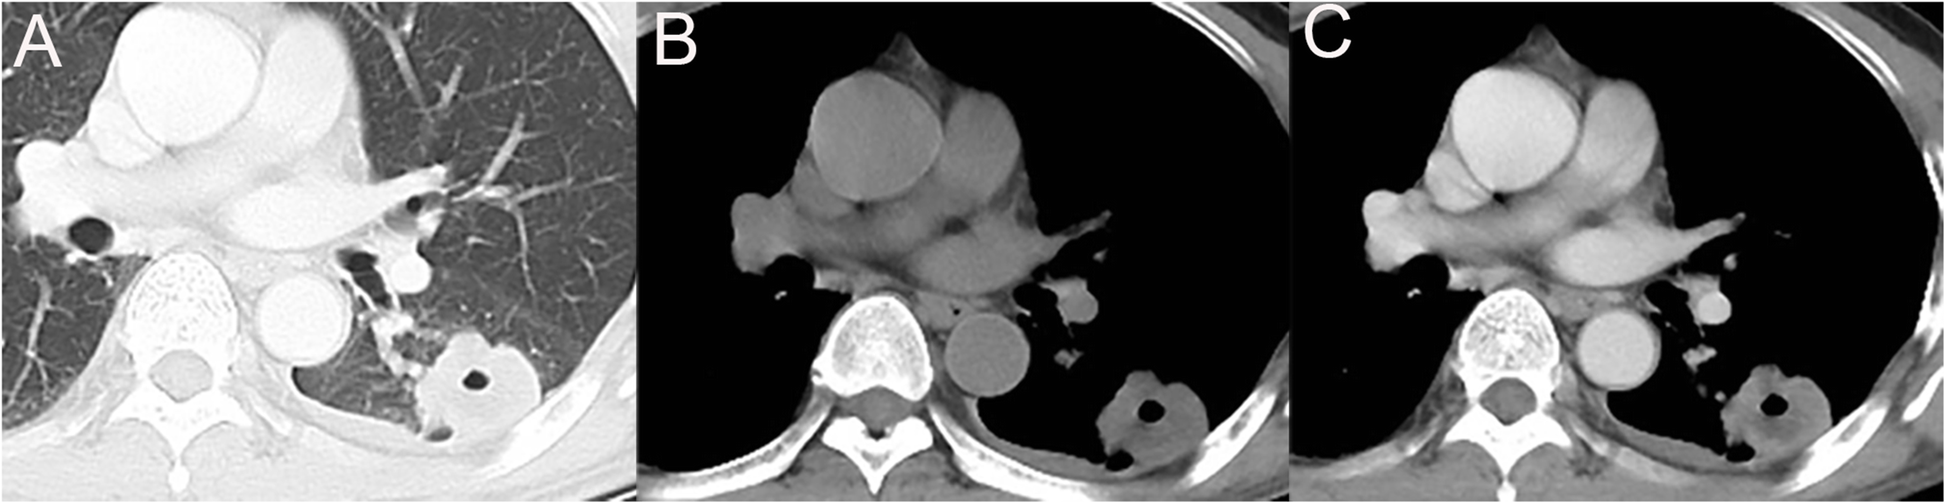

Fig. 2

A PMEC with irregular shape and ill-defined margin with peripheral type. Axial non-contrast CT image (a,b) shows a hypodense mass (arrows) in left inferior lobar dorsal segment. Contrast-enhanced CT image (c) shows tumor with moderate enhancement and necrosis (arrows)